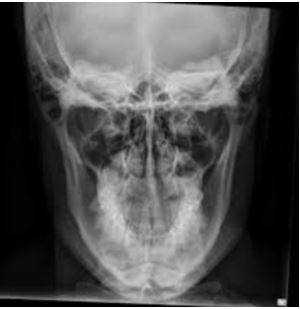

Рентген-диагностика

Прямая и боковая рентгенография челюсти способствует обнаружению опухоли в кости. Новообразование из одонтогенного клеточного материала также хорошо просматривается на рентгенограмме. При наличии опухоли снимок покажет, что зубы не контактируют с костью, а альвеолярный край имеет недостаточно четкий контур.

Отличие КТ челюсти от рентгена

Разница между этими методами инструментальной диагностики довольна большая. Бывают моменты, когда их отличия играют решающую роль в постановке корректного диагноза.

Полученный результат рентген-снимка оценивают исключительно в одной плоскости, что не дает развернутой картины происходящего. Костные образования могут заходить друг за друга, и рентгенолог не всегда может четко отличить накладывающиеся изображения.

Рентгеновский снимок челюсти

низкая стоимость процедуры - исследование часто можно сделать бесплатно в рамках программы ОМС;

широкая доступность - рентген выполняется практически в любой поликлинике;

легкость в исполнении - не требуется переквалификация специалистов, достаточно базового образования в области лучевой диагностики;